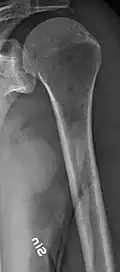

The diagnostic examination of a person with suspected multiple myeloma typically includes a skeletal survey. This is a series of X-rays of the skull, axial skeleton, and proximal long bones. Myeloma activity sometimes appears as "lytic lesions" (with local disappearance of normal bone due to resorption) or as "punched-out lesions" on the skull X-ray ("raindrop skull"). Lesions may also be sclerotic, which is seen as radiodense.[76] Overall, the radiodensity of myeloma is between −30 and 120 Hounsfield units (HU).[77] Magnetic resonance imaging is more sensitive than simple X-rays in the detection of lytic lesions. An MRI may supersede a skeletal survey, especially when vertebral disease is suspected. Occasionally, a CT scan is performed to measure the size of soft-tissue plasmacytomas. Nuclear Medicine Bone scans are typically not of any additional value in the workup of people with myeloma (no new bone formation; lytic lesions not well visualized on nuclear bone scan).

Multiple myeloma in the upper arm -

Femur with multiple myeloma lesions -

Same femur before myeloma lesions for comparison -

Humerus with multiple myeloma lesions -

Same humerus before, with just subtle lesions